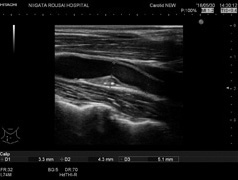

2)頚動脈超音波検査

動脈硬化の程度を調べる検査です。また、脳血管疾患に対する評価も用いられます。 動脈硬化を起こすと血管壁が厚くなったり硬くなったりします。

![]() |

|

| 頸動脈超音波画像 | 下肢静脈画像 | |